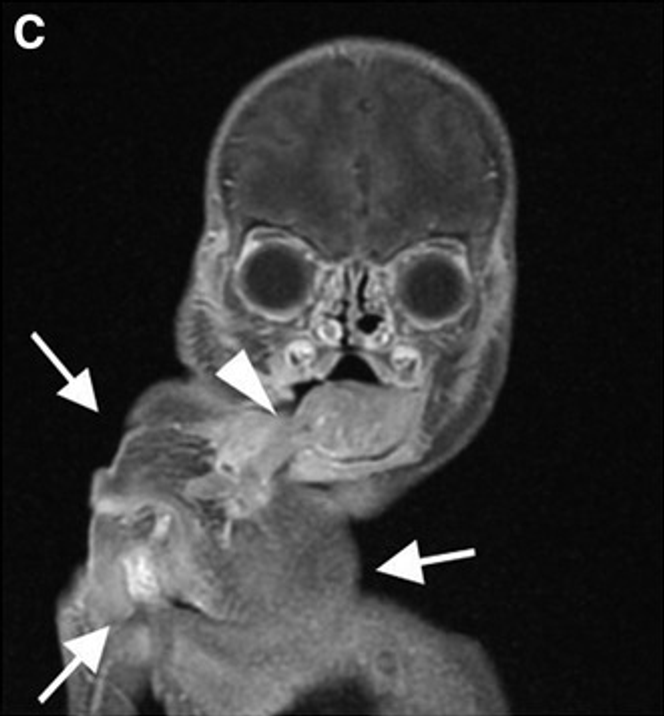

Le nouveau-né va immédiatement confronter les médecins à une situation d’une extrême rareté : la présence de deux masses fœtiformes. L’une est située dans la région maxillaire, déformant la mâchoire gauche et provoquant le déplacement du globe oculaire vers l’avant (exophtalmie). L’autre, située dans la cavité buccale, obstrue partiellement les voies respiratoires. Il s’avère que cette masse, qui sort littéralement de sa bouche, est un jumeau parasite, ce qu’on appelle un fœtus in fœtu.

L’examen clinique révèle donc deux masses fœtiformes. L’une déplace le globe oculaire gauche tandis que l’autre correspond à une tumeur épignathe obstruant partiellement les voies respiratoires. Ce bébé a donc un jumeau parasite dans la bouche.

L’examen de la masse intra-buccale révèle une structure externe et interne étonnante. Recouverte de peau et de cheveux, on distingue une ébauche de pavillon auriculaire, une ébauche d’orbite oculaire, un appendice évoquant un membre rudimentaire, une formation osseuse, des zones graisseuses, gélatineuses et kystiques.

Au microscope, les anatomopathologistes identifient une colonne vertébrale avec des disques cartilagineux, des éléments du tube digestif, une ébauche de membre inférieur et du tissu évoquant un pancréas. Toutes ces caractéristiques convergent vers le diagnostic de fœtus in fœtu.

Un autre cas hors norme a été rapporté par des obstétriciens et pathologistes brésiliens (Rio de Janeiro) dans le numéro daté novembre-décembre 2025 de la revue Fetal and Pediatric Pathology.

Manuella Araújo Couto et ses collègues décrivent le cas d’une jeune femme de 18 ans, enceinte pour la troisième fois, chez qui une anomalie fœtae est détecée par échographie à la 26e semaine de grossesse. Cet examen révèle la présence d’une masse oropharyngée imposante. Cette tumeur faciale mesure plus de 5 x 7 cm.

L’examen externe du fœtus parasite révèle alors une scène saisissante : une tête, entièrement recouverte de peau, émerge de la bouche du fœtus, reliée à lui par un large pédicule.

L’autopsie confirme qu’il ne s’agit pas d’un tératome épignathe (tumeur bénigne sortant de la bouche), mais d’un fœtus in fœtu siégeant dans la cavité buccale.

Une deuxième tête émerge de la bouche du jumeau hôte

Cette structure fœtiforme, qui mesure 10 × 7 cm, comporte des cheveux, des os crâniens, des traits faciaux (deux fentes palpébrales bordées de cils, une structure ressemblant à un nez, une partie de la lèvre supérieure, mais pas d’yeux).

À la dissection, cette « tête parasite » présente deux hémisphères cérébraux peu développés et une hydrocéphalie (augmentation du volume des ventricules contenant le liquide cérébrospinal). Surtout, le cerveau n’est pas relié anatomiquement à la colonne vertébrale du fœtus hôte.